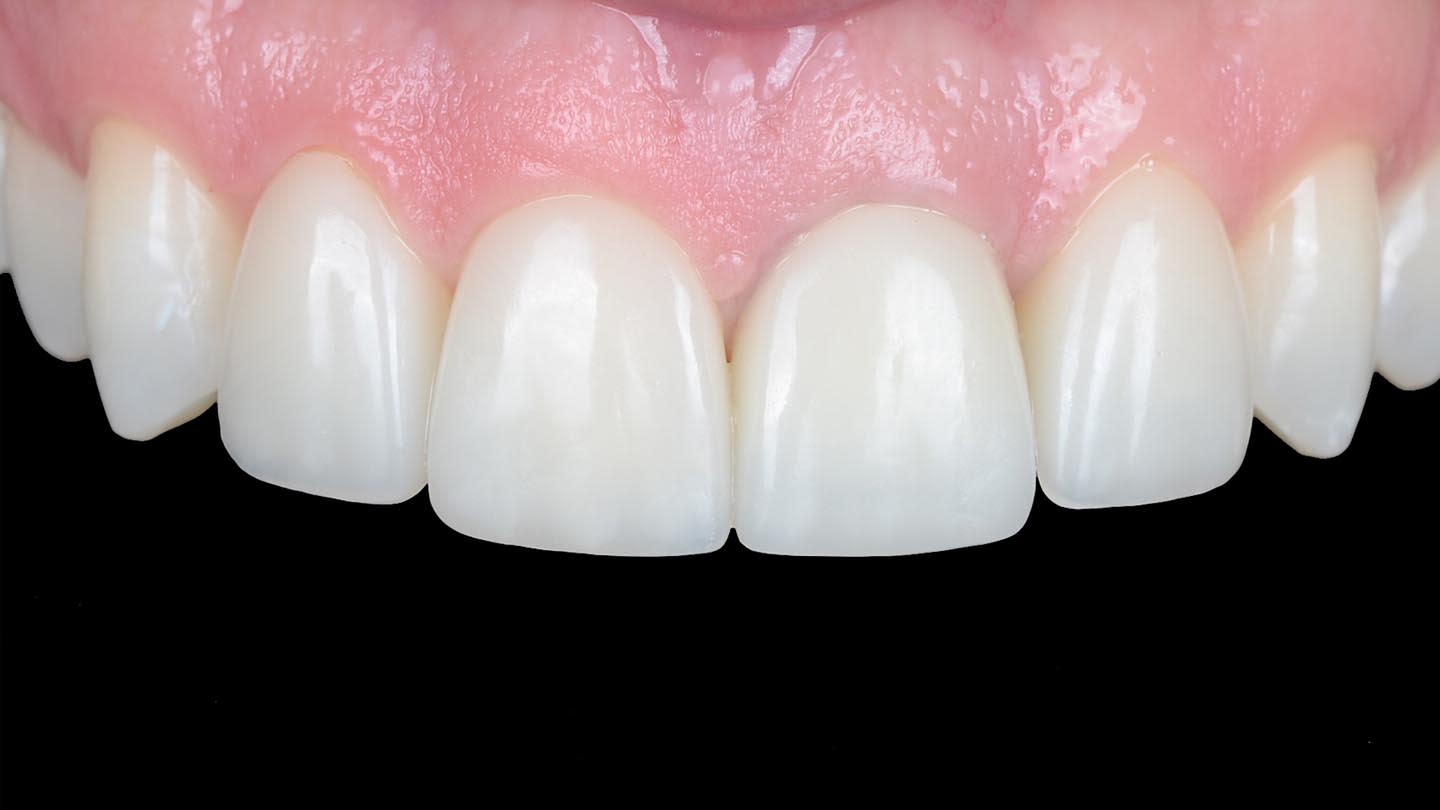

After the luting procedure was completed, a water-based gel was applied to the margins of the restorations to eliminate the oxygen-inhibited layer, and then light-curing was performed for 60 seconds on each veneer. Centric and eccentric contacts were verified using articulating paper. The final results demonstrated the integration of the restorations with natural texture and morphology and an accurate shade matching (Figure 18 and Figure 19). Based on the authors’ experience, these procedures are best performed under magnification.